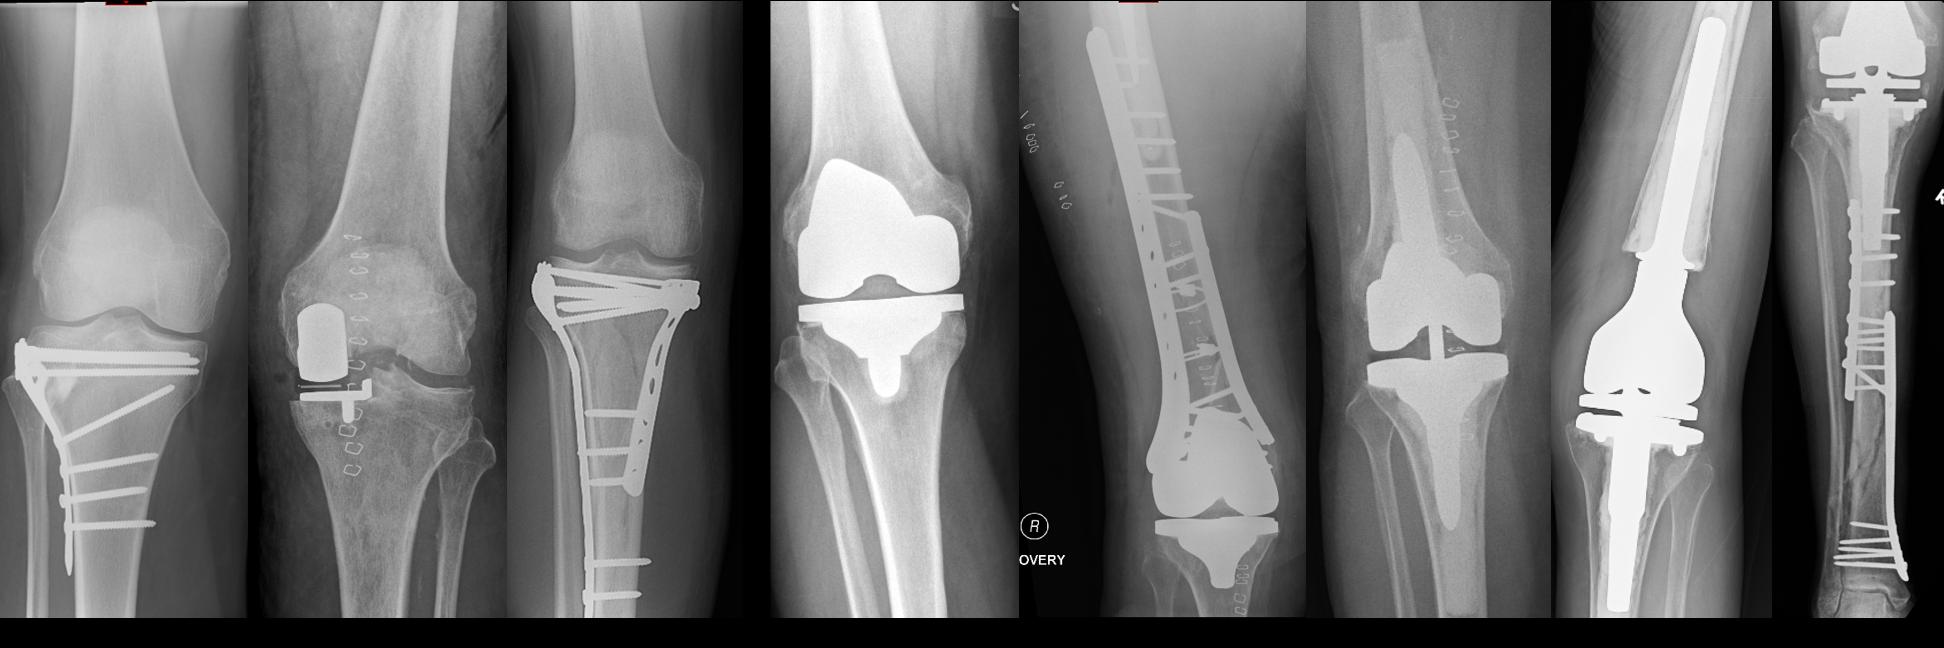

Fix or replace has been the question for distal femur fractures. But what happens when the fixation fails?

This systematic review compares:

• Primary DFR

• Salvage replacement after failed fixation